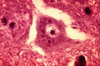

Which tickborne disease enters the brain via a “trojan horse” and results in Acute polioencephalomyelitis, Neuronal degeneration, neuronophagia, Lymphocyte cuffing, gliosis & meningitis?

Louping-ill (Flavivirus) - common in sheep